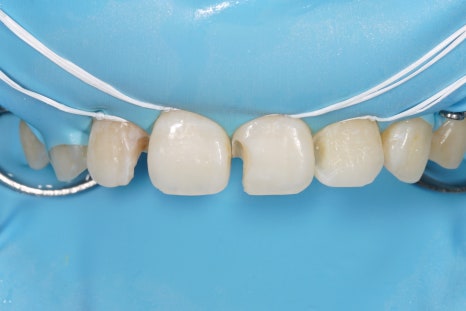

어금니, 앞니 가릴 것 없이

중요한 접착의 순간에

이렇게 러버댐을 사용하는 것,

그래서 구강 내에 있는

뺨과 혀,

피와 침과 습기로부터

치아를 완전히 격리하고 방습하는 것.

그것이 교과서에 적힌 원칙이고

결과를 High-end로 유지할 수 있는

비결입니다.